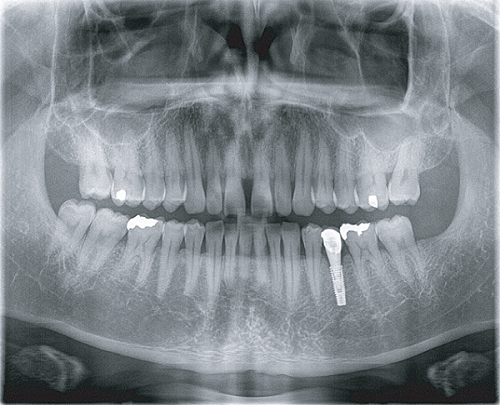

Apsaras 3D 口腔頜面錐形束計算機體層攝影設(shè)備

臨 床 圖 集